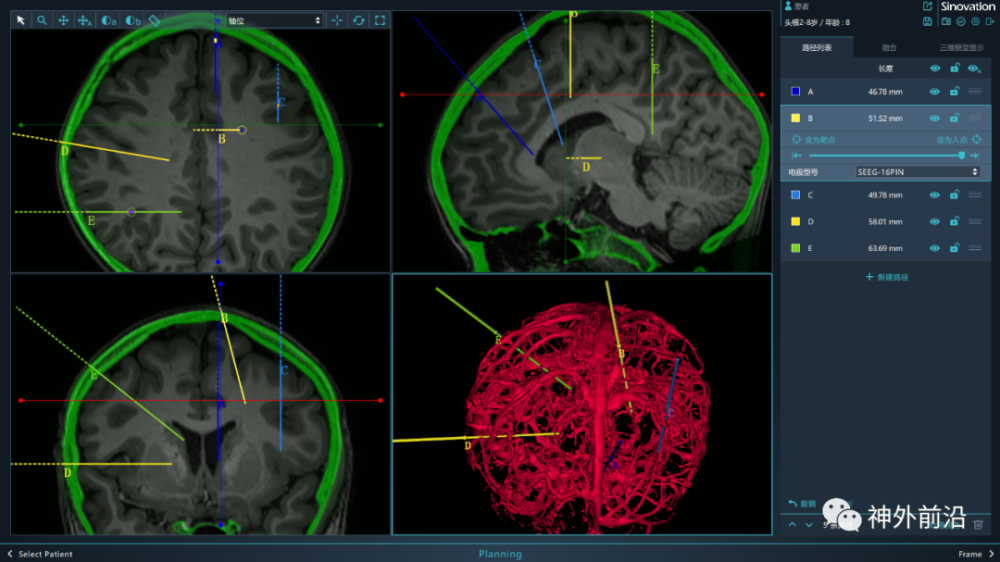

目前临床上还存在一些其他的手术方式:脑立体定向射频毁损术 , 主要适用于下丘脑错构瘤及脑深部局限灰质异位引起的癫痫发作;立体定向放射外科治疗 , 包括γ射线、X射线等 。 以上两种手术方法相关机制 , 更多的适应证尚不明确 , 仍需多中心研究论证 。